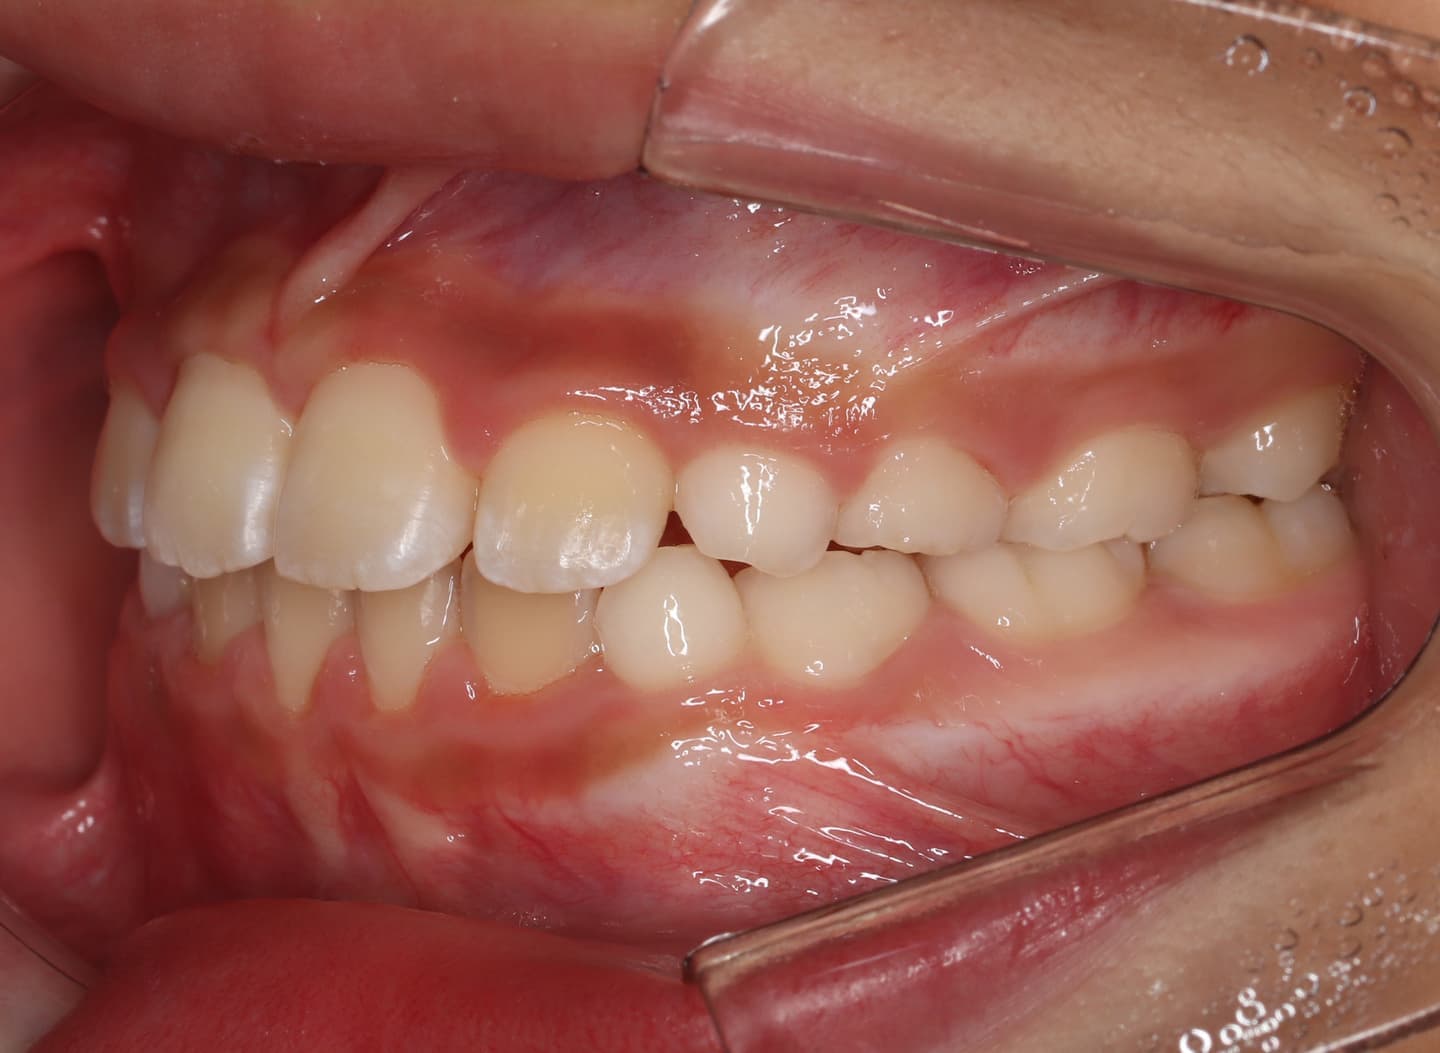

治療後(12ヶ月後)

分析診断:FXフェイシャルアキシスが83度で、咬合力が極端に弱い顔面骨格ではありません。上下顎の骨格的バランスも平均値内には収まっています。Upper Molar PTV値から、上顎の奥行きが少ないとわかります。前歯の位置、E-lineと下唇の位置等から、歯が大きくて顎が小さいディスクレパンシーケースであると診断されます。

分析診断:左右の骨格的非対称が少し認められます。上顔面の幅径はさほど狭くなありませんが、下顎や下顔面の幅径は狭いと出ています。